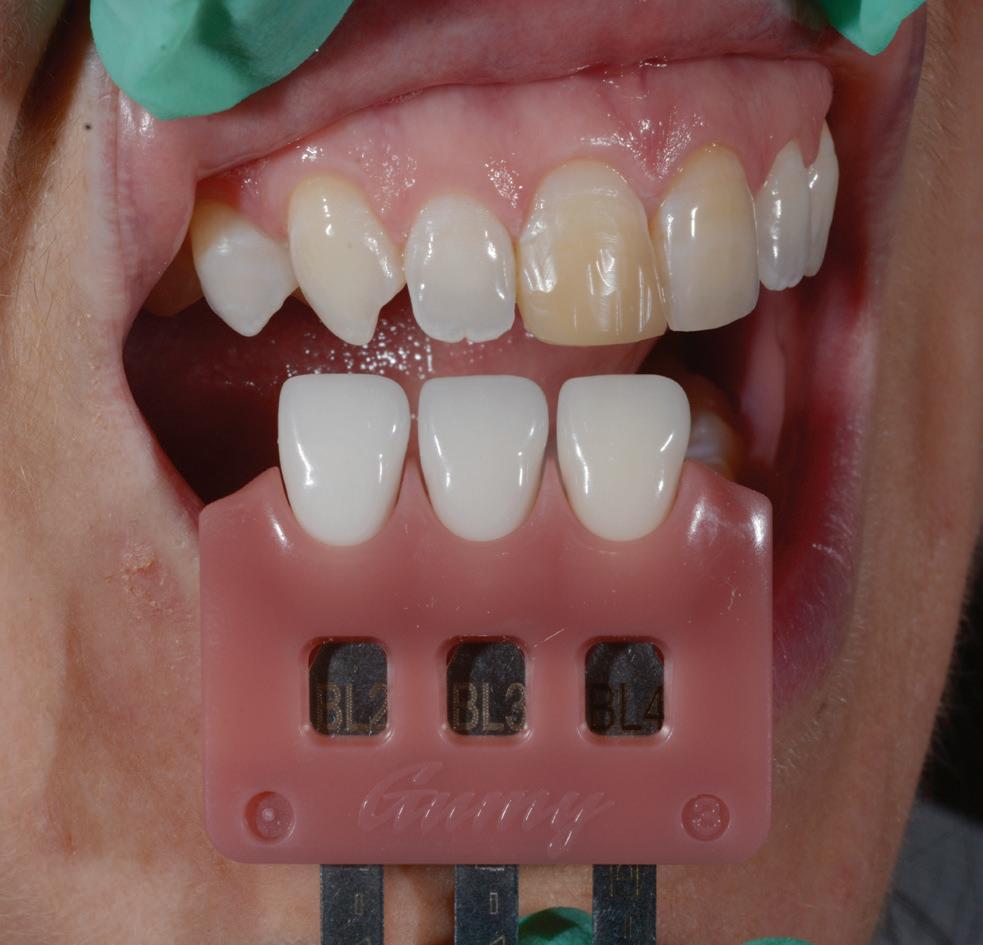

Adopting sharp safe methods is essential in all dental practices. The Ultra Safety Plus and Ultra Safety Plus Twist provides the dental team with the necessary tool to provide safe practice. If sharp safe habits are not expected of each team member, the risk of a sharp injury increases.